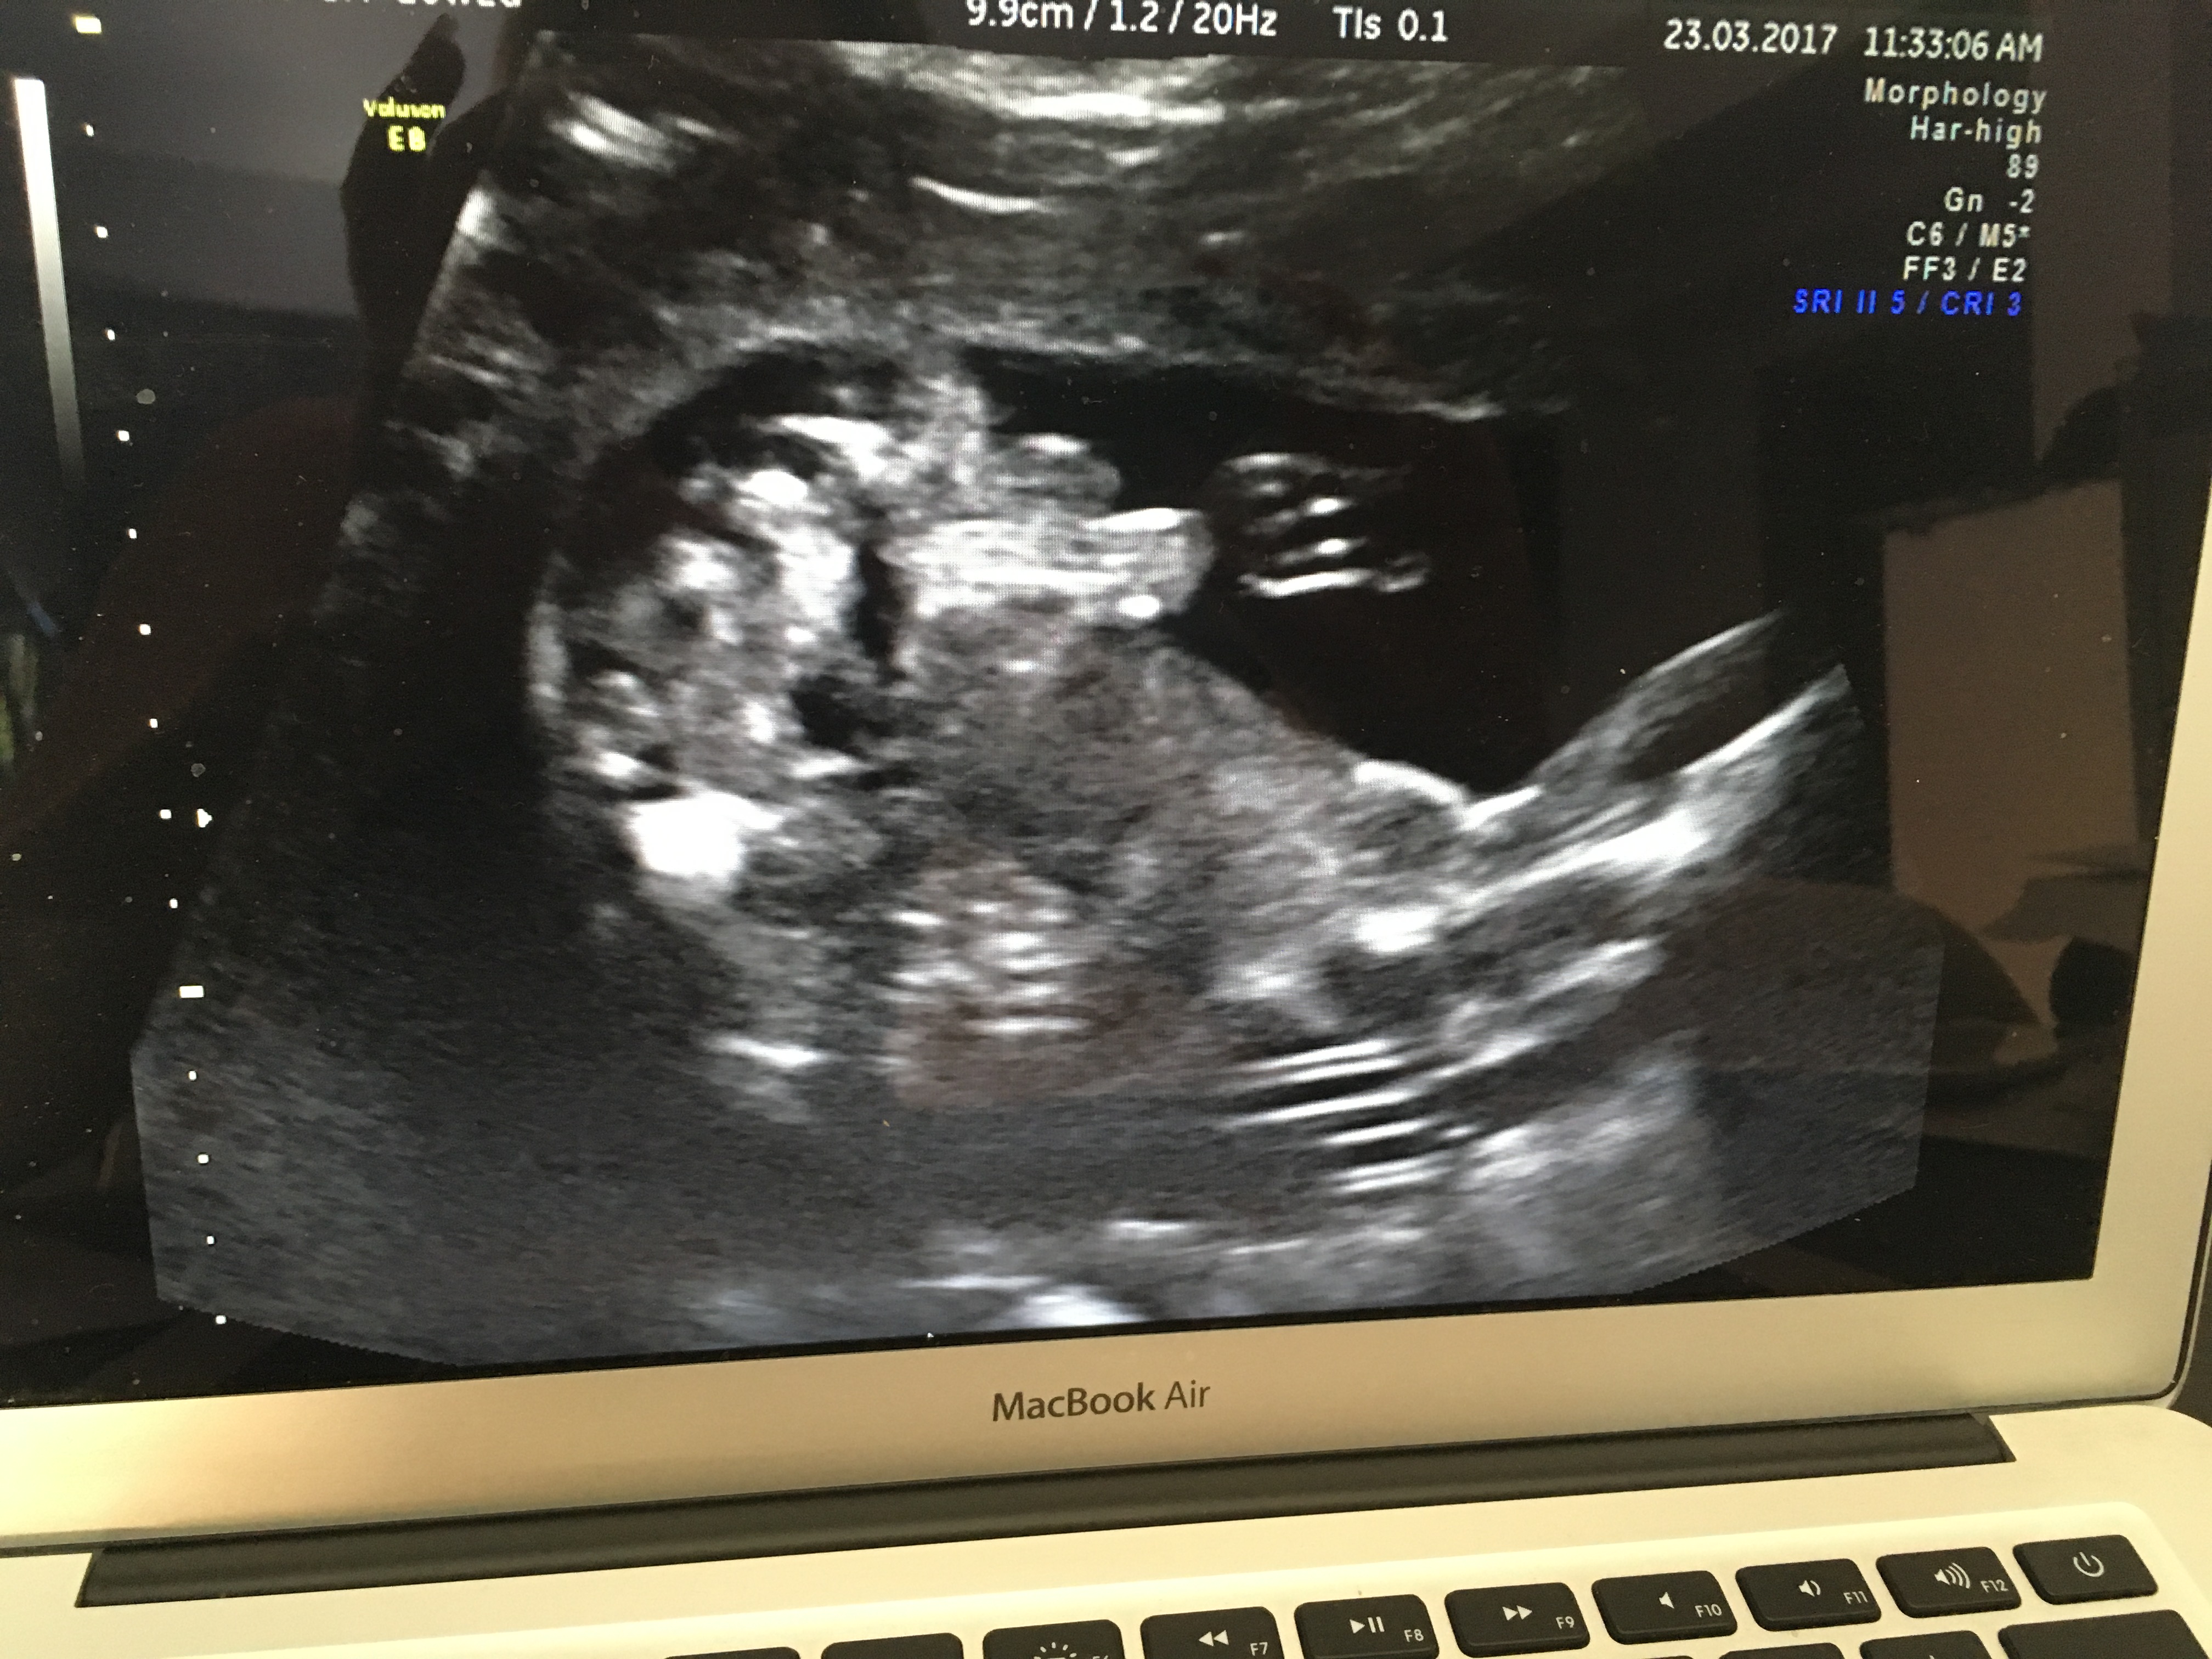

What do you think? Sonographer said confidently boy but I can see lines and think it could be swollen labia? Cord is also around baby's legs as you can see in 4d pic. Attachment 35555Attachment 35556Attachment 35557

Looks like a boy to me :) Boys can also have 3 lines. Were you hoping for a girl?